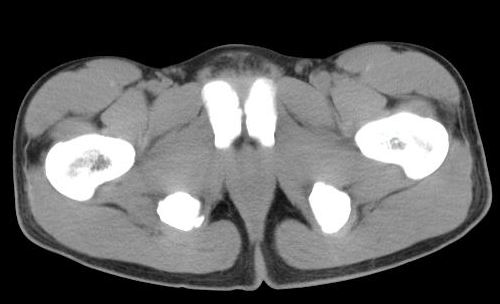

男性,15岁,半年前曾有做运动摔伤史,伤后左肢麻木,一天后恢复,两个月后因右臀部隐痛照片示右坐骨下骨性密度影,现复查见骨性影无明显改变。求助诊断!

坐骨粗大,有瘤骨,基地部有囊状骨缺损。不应为外伤史迷惑,应考虑外生软骨瘤病或骨膜硬纤维瘤。请勿见笑。

坐骨撕脱性骨折伴骨化性肌炎

如果是撕脱骨折,应该有疼痛,而病史是伤后左肢麻木,一天后恢复,两个月后因右臀部隐痛才就诊,病变在肌肉区,故考虑骨化性肌炎

支持坐骨撕脱性骨折合并血肿机化、骨化。

坐骨陈旧性撕脱性粉碎性骨折伴骨痂形成.